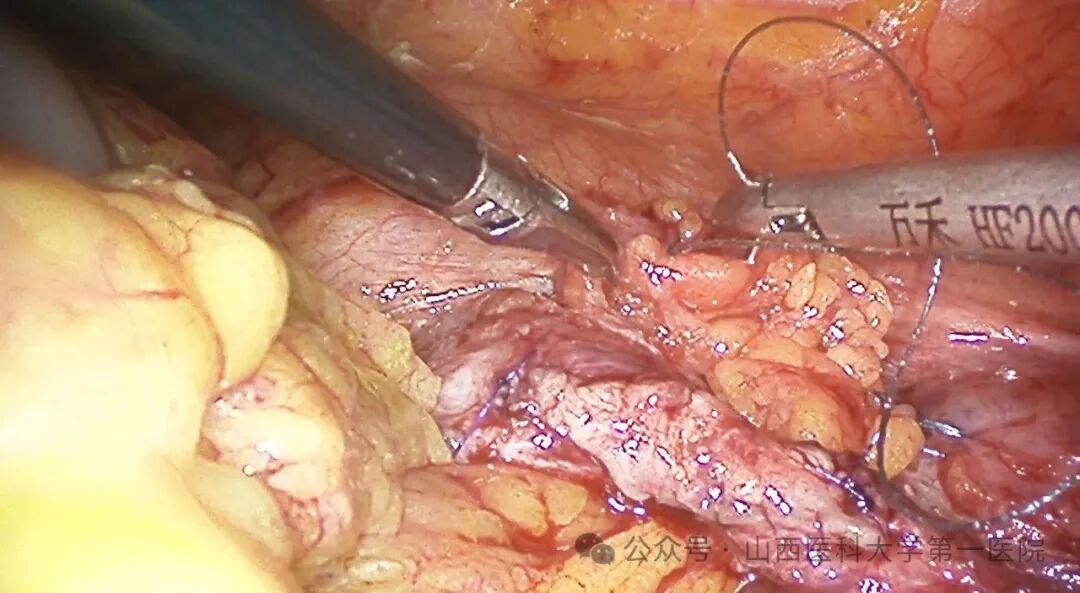

在明确狭窄段并充分游离后,术中发现狭窄段长约1cm,管腔闭锁,瘢痕组织坚硬。考虑到单纯吻合张力过大,团队决定采用口腔黏膜补片扩大成形术,在孟兵的协助下成功切取患者颊粘膜组织,郭华杰将口腔黏膜补片缝合于输尿管狭窄段缺损处,有效扩大了输尿管管腔。

切除输尿管狭窄段+后壁重建+放置双J管